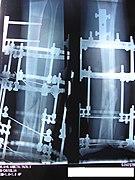

The following case study illustrates the Ilizarov apparatus treatment procedure for a fractured limb. The photographs are of the same patient during the course of treatment.

Front (top) view with a view of the healthy leg. The patient is lying on his stomach.